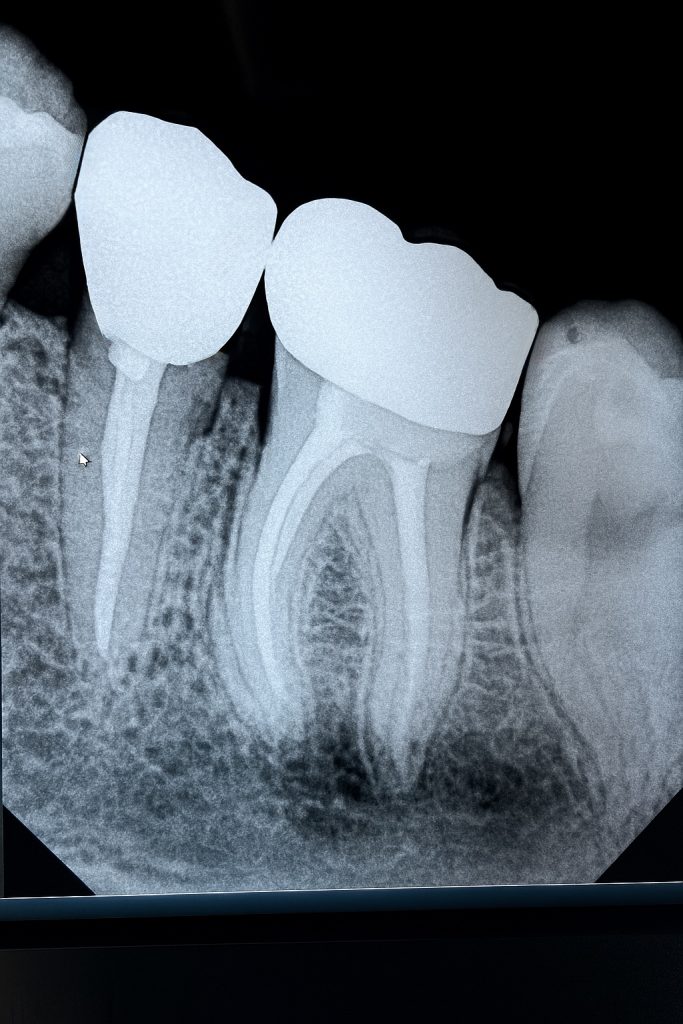

4. Obturation

Obturation performed with Bioceramic Sealer (Endo Sequence BC) and warm vertical condensation to ensure apical seal and coronal adaptation (Fig 3).

7. Post-Operative Evaluation

Radiograph confirmed ideal obturation, core adaptation, and marginal integrity (Fig 3). The final restoration blended esthetically and functionally with the dentition (Fig 5).

- Fig 3: Post-obturation radiograph confirming dense 3-D fill.